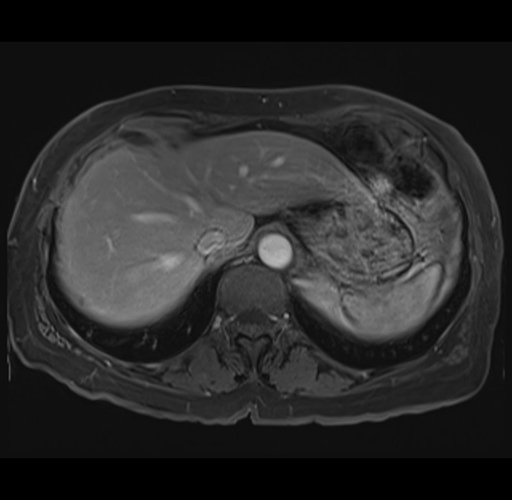

MRI T1

Imaging analysis

Based on your CT findings, which issue(s) would give reason for "planned slowing down moment(s)" in this case?

Considering a standard right hepatectomy procedure, what step(s) of the operation would you do differently in this case?